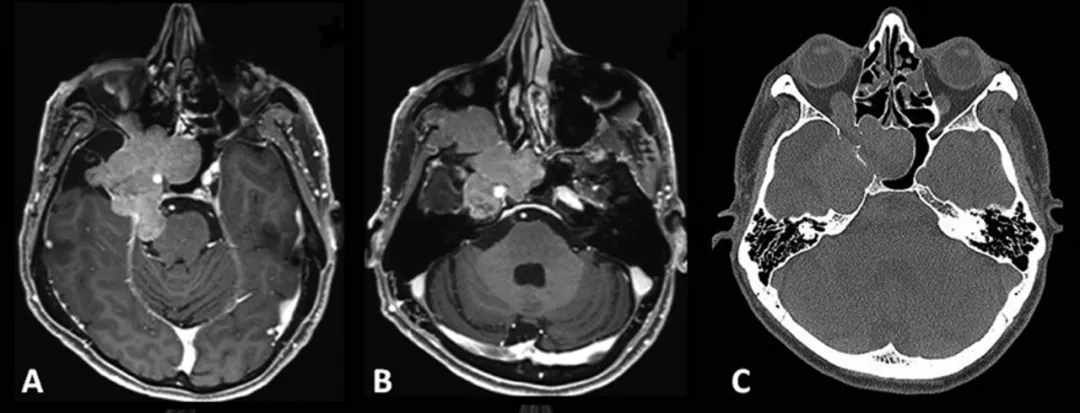

患者术前影像。(A)术前轴位T1加权钆增强磁共振成像(MRI),显示脑膜瘤延伸至后颅窝(PF)、海绵窦(CS)、眼眶和蝶窦(SS)。(B)肿瘤延伸至中颅窝、翼腭窝(PPF)和颞下窝(ITF)。(C)术前轴位计算机断层扫描(CT)显示蝶骨大翼侵蚀和蝶窦(SS)受累。

该患者的磁共振成像(MRI)检查结果显示,原先的脑膜瘤已经复发,并且肿瘤体积增大,其生长范围已经扩展至多个关键区域。具体而言,肿瘤复发部分侵入了海绵窦(cavernous sinus,CS),这个结构周围有许多关键的神经和血管;同时,肿瘤还延伸至后颅窝(the posterior fossa,PF),这是一个包含脑干和小脑的重要区域;此外,肿瘤还扩展到了蝶窦(sphenoid sinus,SS)、翼腭窝(pterygopalatine fossae,PPF)以及颞下窝(infratemporal fossa,ITF)。这些区域的受累不仅加剧了患者的临床症状,也为手术治疗带来了额外的挑战。